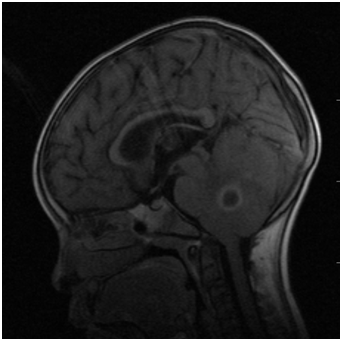

A 6year old boy weighing 14kg (expected weight=20kg) was referred to the neurosurgical unit of University College Hospital, Ibadan, with complaints of headache, vomiting, fever and unsteady gait of one week duration. There was no history of ear ache or ear discharge, scalp infection, trauma, seizure or any other systemic disorder. He was diagnosed to have multiple right cerebellar hemispheric abscesses based on Magnetic Resonance Imaging (MRI) finding of rings enhancing masses in the cerebellum (Figures 1) (Figure 2). He is a known patient of the paediatric Cardiology unit with uncorrected congenital heart defect. Pregnancy birth and neonatal history were uneventful until 5months of age when he was diagnosed with congenital heart disease and has been on follow up until this present illness. He has never been in heart failure and was not on any cardiac medication. Patient was awaiting surgery for the heart defect when he developed this present illness. His physical examination revealed a small for age child, afebrile, not pale, anicteric but has central cyanosis and peripheral oxygen saturation (SpO2) was 85% in room air with grade 2 digital clubbing.

Figure 1 MRI showing the cerebellar abscess.